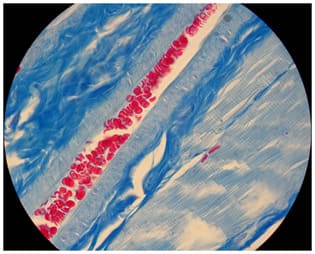

Own longitudinal and transverse specimens of the rat triceps surae muscle Gomori and Azan stained and US images of normal muscles. They were analyzed to visualize and confirm or deny knowledge about striated muscles’ tendinous system. Tendinous system consists of tendons, endomysium and perimysium (Figures 1,2). Within any striated muscle understood as a structure between origin and insertion there is no place where there wouldn’t be a tendinous tissue. So muscle in fact is a tendon delaminated at the belly level to host myofibers (Figure 2).

Histological specimens show that the tendons loose their mass as they go along the muscle belly (Figure 3). That is due to the fact that tendinous fibers detach from the tendon and without any junction cover the whole myofiber as loose connective tissue (Figures 4,5).

The only way the myofiber attaches to tendinous system is a parietal myotendinous junction (PMTJ) (Figures 5,6,7).

Histology-US Correlation

The whole tendinous system can be clearly visualized by ultrasound. The tendons as well as perimysium+endomysium show in a relaxed muscle as hyperechogenic lines of different thickness. Skeletal muscles show 0,1-0,4mm of anechoic space between the bright lines and that is 4 to16 myofibers (depending of the size of myofibers) per dark space between the lines of endomysium + perimysium in a relaxed state, neutral position. Figures 17,18,19 show the US images of selected muscles.